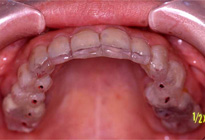

●初診時口腔内

数件の歯科医院で治療を受けられましたが、噛み合わせが合いませんでした。その度に補綴物をやり直すも、結局外してしまい、当院へ来院されました。右半身を中心に肩こり、首こり、顎の痛みを訴えられています。